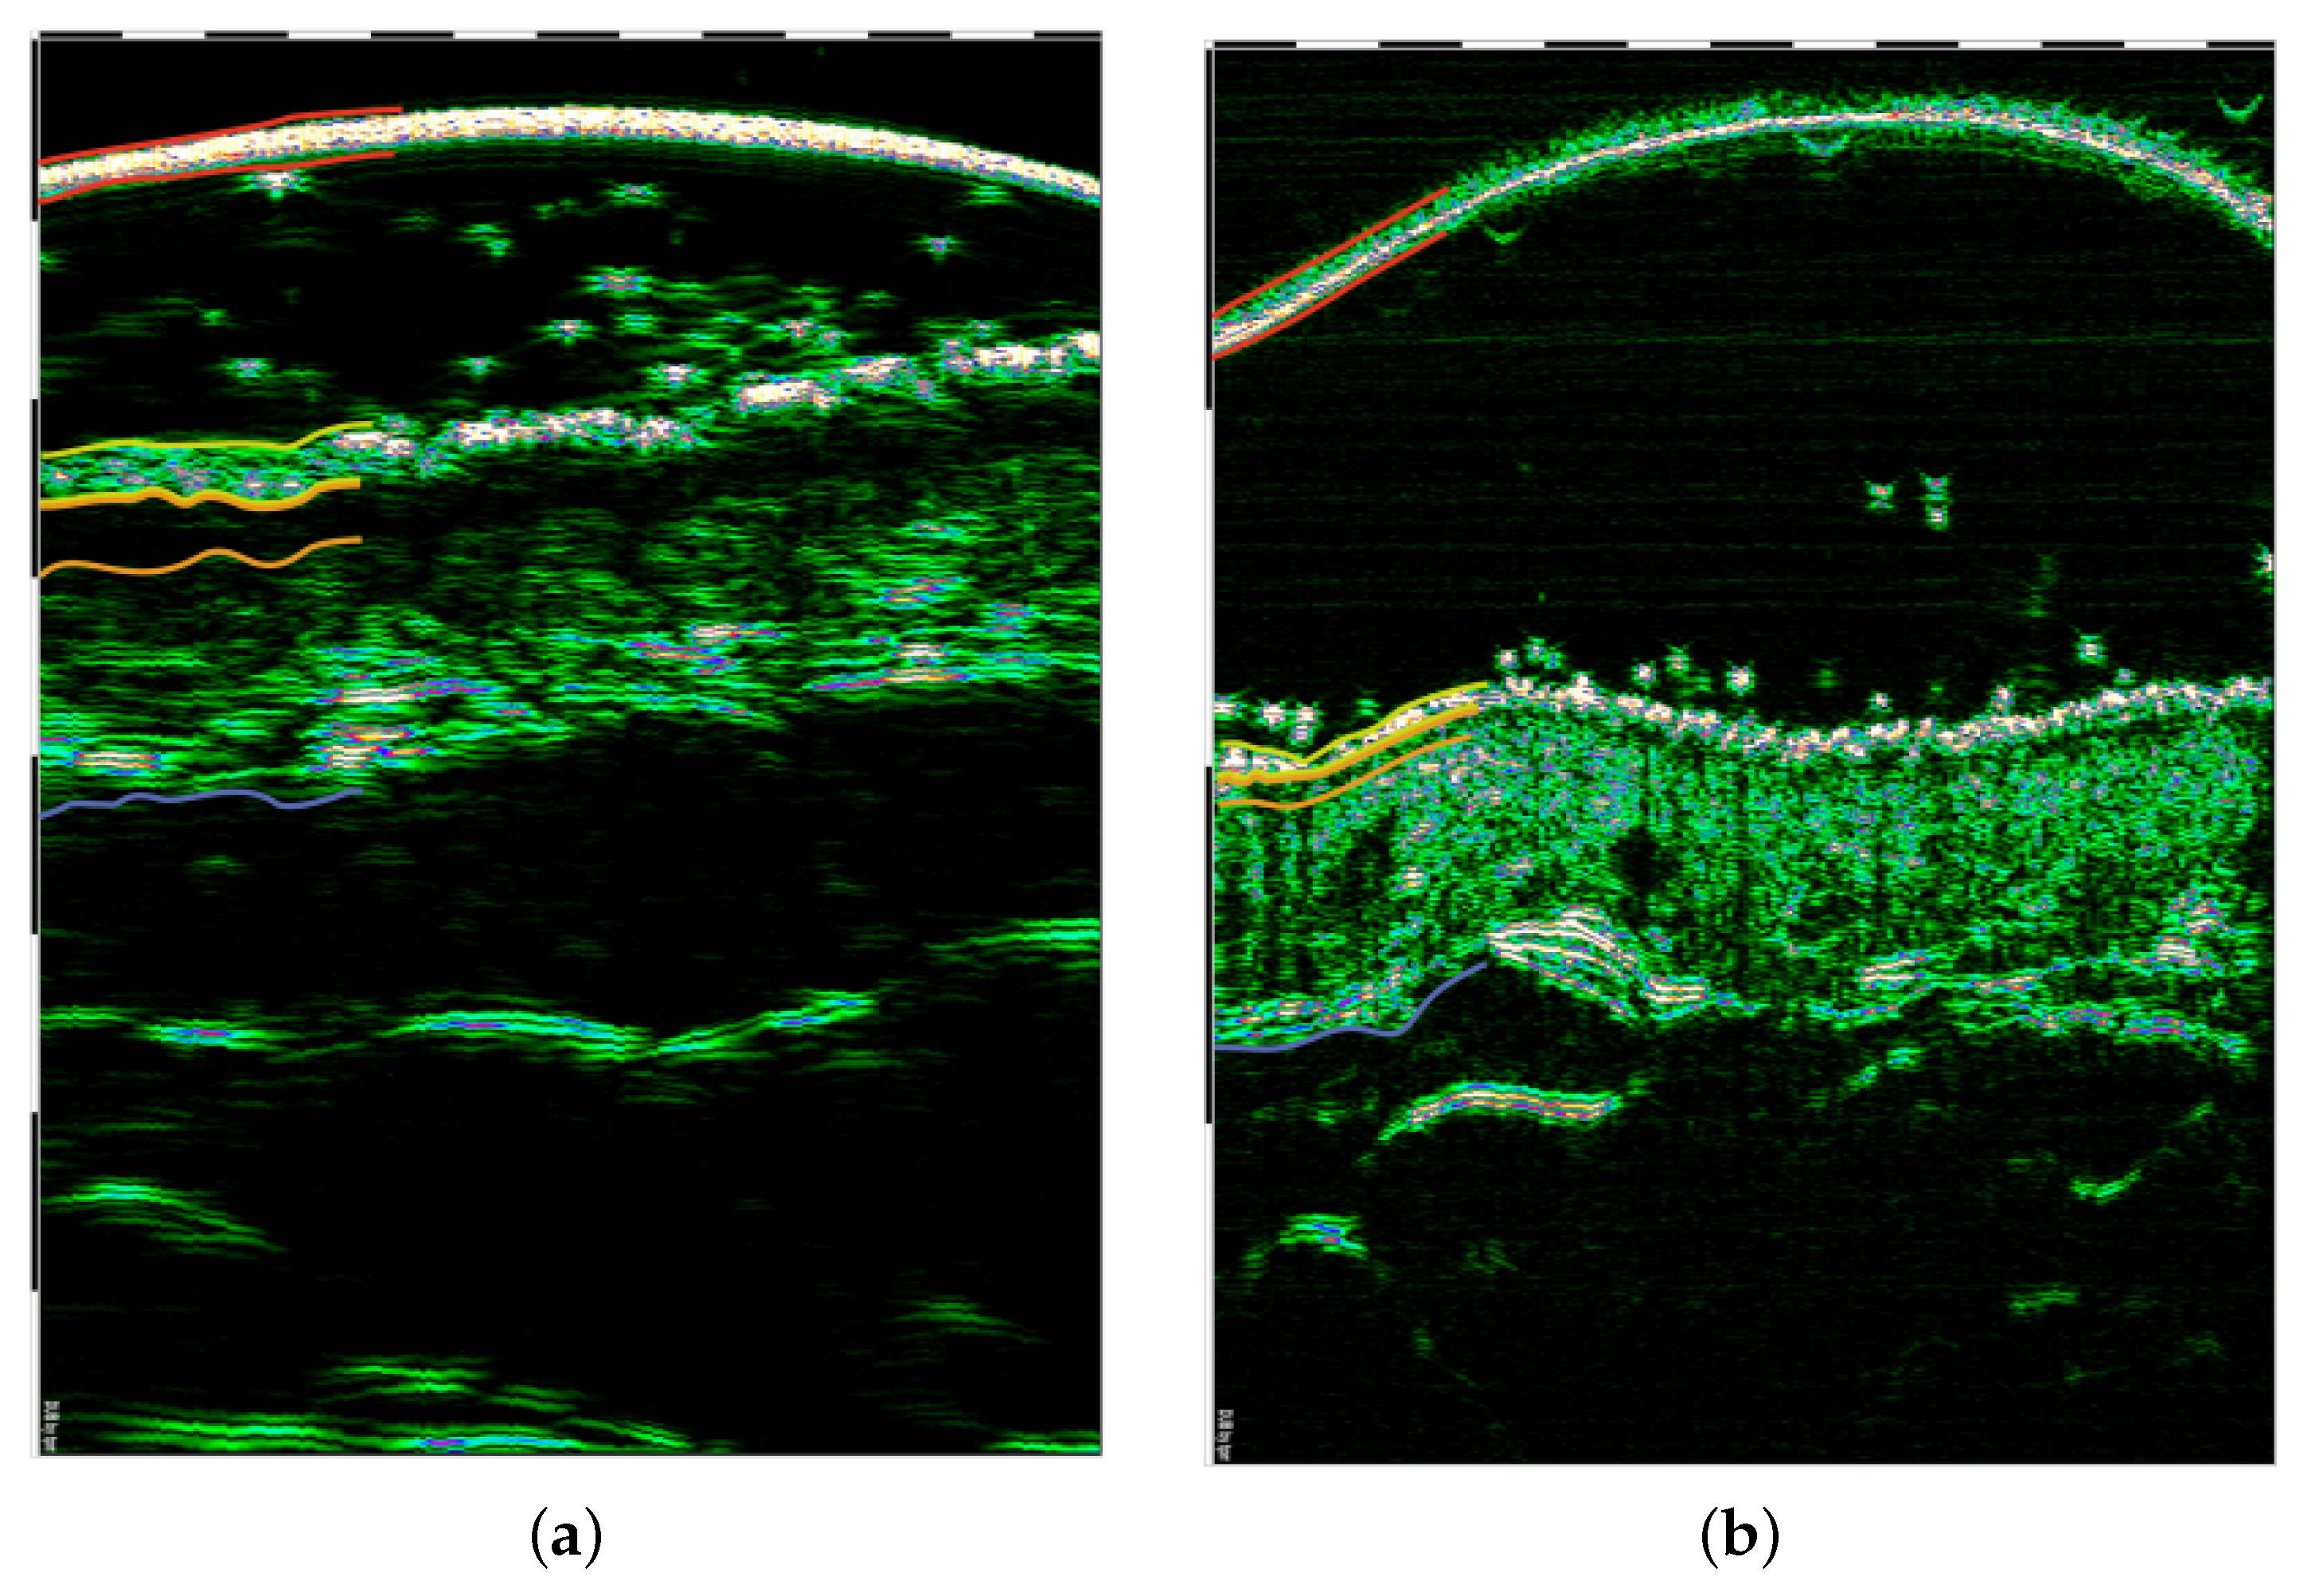

4.1. Skin Layer Segmentation

4.1.1. Classical Approach or Small Datasets

- A few classical methods deserve special attention: [10,15,17,48]. The first two [10,15] applied level-set techniques, which resulted in a Dice index equal to 0.94 and 0.878, respectively, which is a high result for medical applications. The Dice index equal to 0.878 described in [15] places this work far behind [10]. However, the obtained mean absolute distance value (8.5 m) was, in this case, much lower than that calculated by Sciolla et al. (45 m), and this parameter seems to be more relevant for clinical diagnoses.

- Among all the CNN-based solutions, that in [48] is particularly noteworthy, as the authors applied the common U-shape models for both the epidermis and SLEB segmentation. The obtained accuracy (median(D) ≥ 0.93) for the DC-UNet model developed by Lou et al. [71] is at the level of clinical acceptance.

- Since the authors did not present the whole datasets or representative samples visualizing the differences in the analyzed images, it was hard to assess the adaptability of the described methods to other types of data. For example, the level-set method described in [15] when applied to a bigger dataset (380 images [67]) in [3] resulted in a median Dice index equal to 0.727 for the epidermis and 0.54 for the SLEB. For the comprehensive dataset analyzed in [17], which included different diseases, the CNN-based segmentation results were lower than for the inflammatory one.